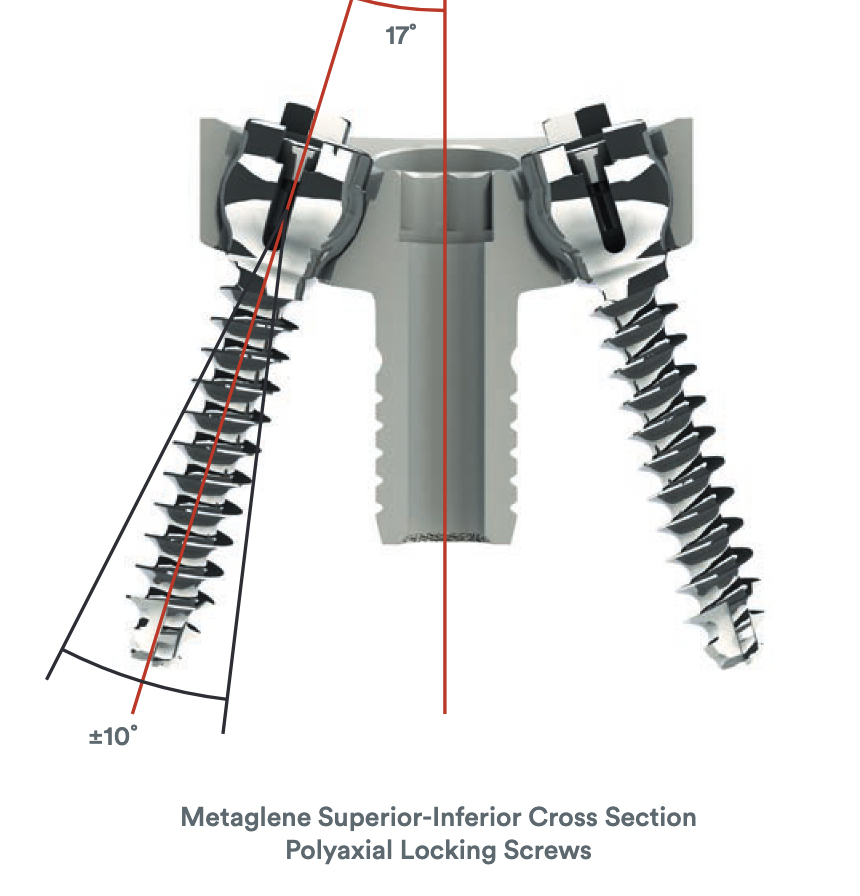

Metaglene / baseplate fixation

Screws as long as possible

- inferior screw - long into scapular pillar

- superior screw - aim for coracoid

- anterior / posterior screws - convergent / divergent

Depuy Synthes Delta Xtend